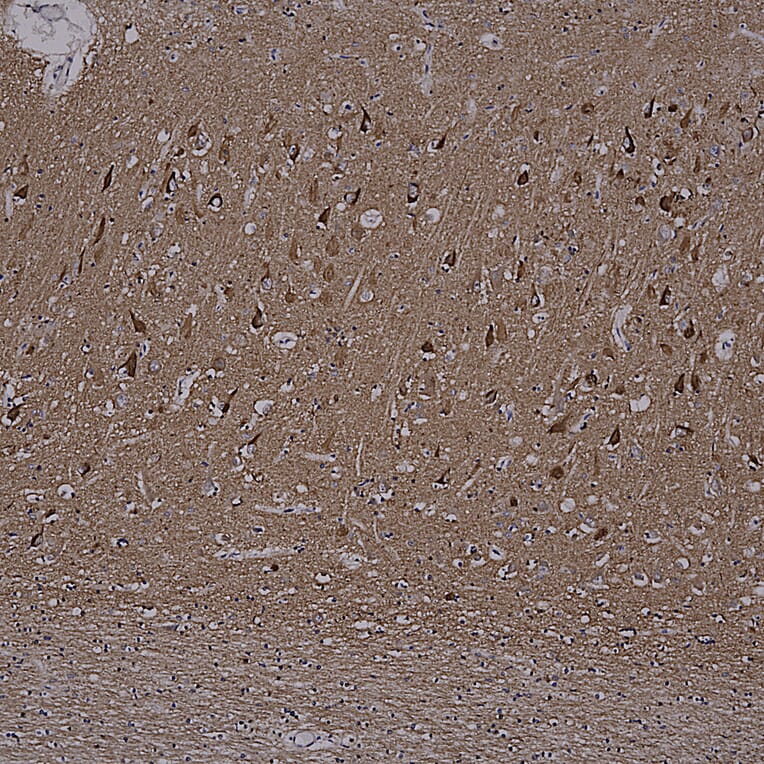

Immunohistochemistry analysis of a NBF fixed paraffin embedded human brain hippocampus section from an Alzheimer’s Disease case. Mouse mAb to MAPtau, Anti-Tau Antibody [2E9] (A85416) at a dilution of 1:1,000, was detected in DAB (brown) using the Vector Labs ImmPRESS method and reagents with citra buffer retrieval. Counterstained with Hematoxylin (blue). The Anti-Tau Antibody [2E9] (A85416) strongly labels cell bodies in diseased neurons and is ubiquitously expressed at a lower level in most cells types. Note: this antibody performs well in testing with 4% PFA or standard NBF fixed human and rat tissues.